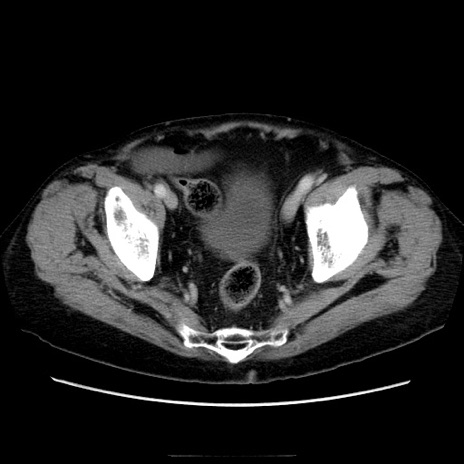

症例21(横断像)

【症例】70歳代男性

【主訴】腹痛

【現病歴】肝硬変・肝細胞癌にてかかりつけの方。約9時間前に食後より腹痛出現。症状が徐々に増悪し、嘔吐出現したため来院。

【既往歴】肝硬変、肝細胞癌(RFA、TACE後)

【身体所見】意識清明、表情苦悶様、BT 36℃、BP 129/78mmHg、P 88bpm、SpO2 97%(RA)、右上腹部から心窩部にかけて圧痛あり、反跳痛なし、筋性防御あり。

【データ】WBC 5800、CRP 0.16